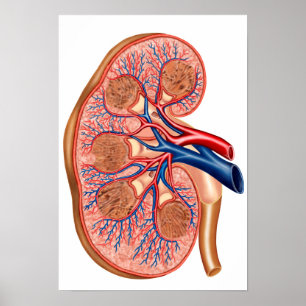

Carta do poster da anatomia do órgão interno do

Preço56,50 €

Impressão humano da anatomia dos órgãos interno

Preço15,60 €